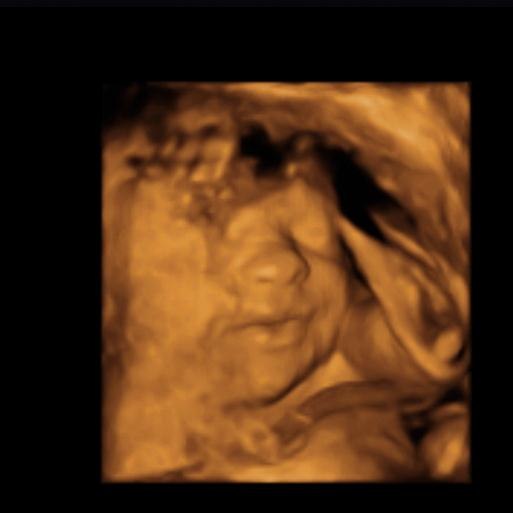

Vi var i fredags til scanning hvor jeg var 16+1 og det var en super fed oplevelse, selvom den lille var genert

vi ønsker ikke at vide kønnet, så er jo dejligt vi alligevel kunne få lov at opleve 3D

Vedhæftede fotos (klik for at se i fuld størrelse)